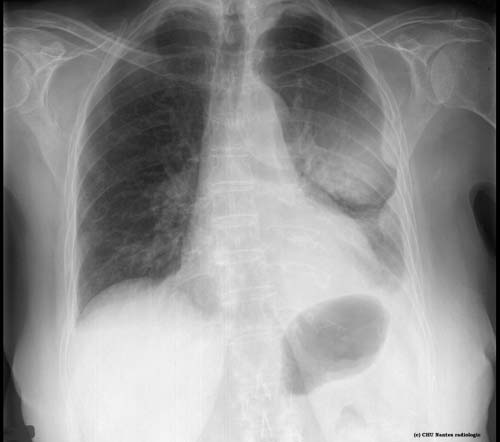

Masses pleurales

légendes